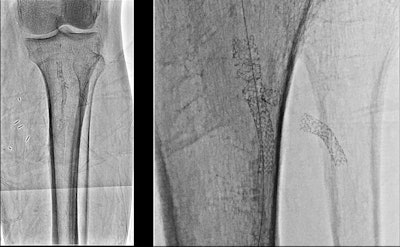

Image of a stent in popliteal and anterior tibial arteries: standard resolution with 12-inch field-of-view (left) and Hi-Def resolution with 3-inch field-of-view (right).Hi-Def uses a combination of detector materials for normal and high-resolution operation, with amorphous silicon for conventional resolution and crystalline silicon in high-resolution mode. Users can switch back and forth with a single button push, with the high-resolution mode available in 3-, 2.3-, and 1.5-inch views.